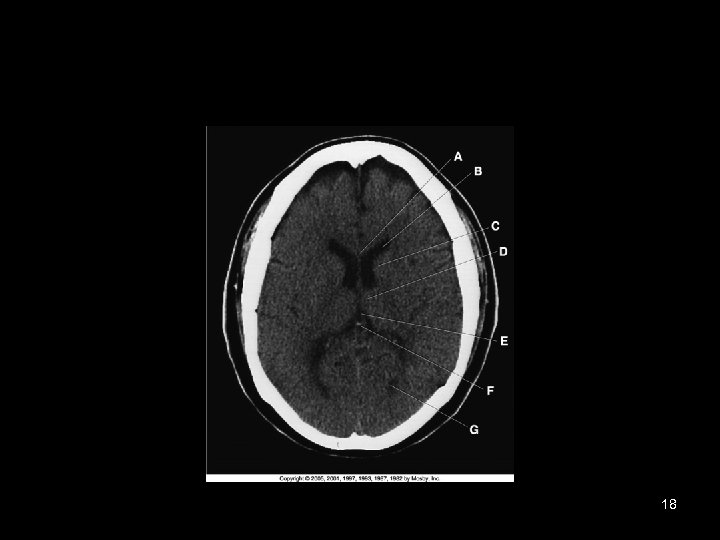

18